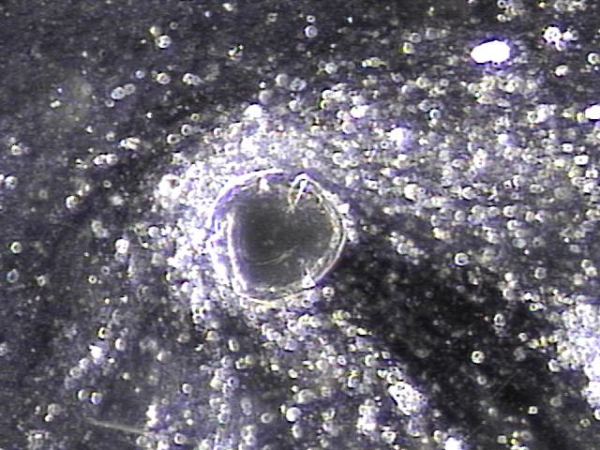

내원 당일 전립선의 표적 치료후 배출된 전립선액의 배양과 PCR 검사를 한후 현미경학적 검사상 치료된 사정관 결석과 전립선의 결석 자료입니다.

On the day of the visit, following targeted prostate treatment, prostatic fluid was discharged and analyzed through culture and PCR testing. Microscopic examination revealed treated ejaculatory duct stones and prostatic calculi.

전립선과 사정관 그리고 사정관입구의 결석 치료중 사정관의 좁은 입구와 전립선관의 막혀 있는 입구로 커다란 결석이 배출시 압력으로 좁아져 있거나

막혀 있던 섬유화된 입구의 손상이 예상되는 현미경학적 사진입니다.

This is a microscopic image taken during the treatment of stones in the prostate, ejaculatory ducts, and the ejaculatory duct orifices.

It shows that large stones being expelled through the narrowed or obstructed fibrotic openings of the ejaculatory and prostatic ducts likely caused mechanical damage due to pressure during expulsion.